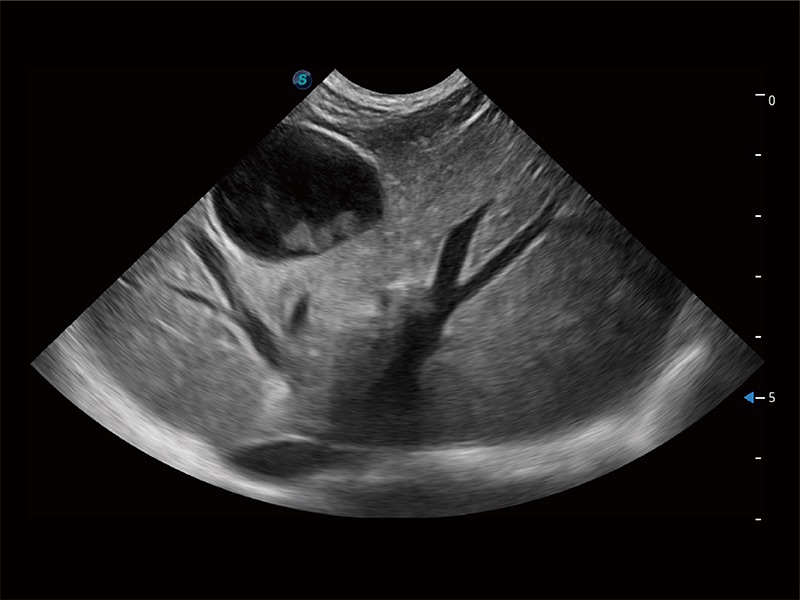

动物是人类最亲密的朋友和最值得信赖的伙伴。DB中国旗舰官方网站也一直致力于探索动物专用的超声影像解决方案。全新推出的ProPet系列,是DB中国旗舰官方网站在动物超声影像智能化、专业化、精准化的一次跨越式革新。动物不能用言语来表述自己的不适,通过超声影像,ProPet系列搭建了动物医生与不同物种沟通的“桥梁”,为动物医生注入了“治愈之力”。 ProPet 80 是DB中国旗舰官方网站匠心打造的一款高端动物专用彩超,采用性能卓越的全新硬件架构,极大提升超声系统的运行效率和数据处理能力,帮助动物医生从容应对日益增多的挑战性病例和日益多样化的临床需求。

高性能和先进的临床应用工具可以为动物医生提供临床信心。ProPet 80 搭载了先进的腹部和浅表应用工具,帮助医生在日常临床实践中发挥前所未有的作用。

ProPet 80 全新的动物超声智能软件和丰富的探头群,为动物医生提供了高清晰度和精细分辨率的图像,无论在宠物、马科、畜牧还是实验室动物等应用中都可以轻松应对,为您的日常工作带来满意的体验。